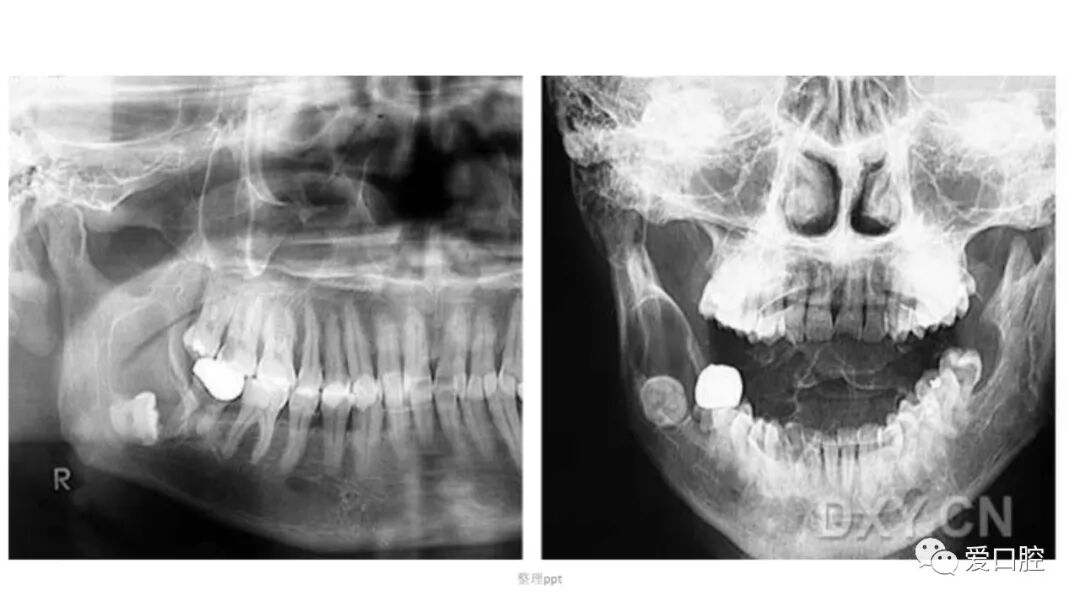

口腔小技巧 | 口腔科常见的病例影像!